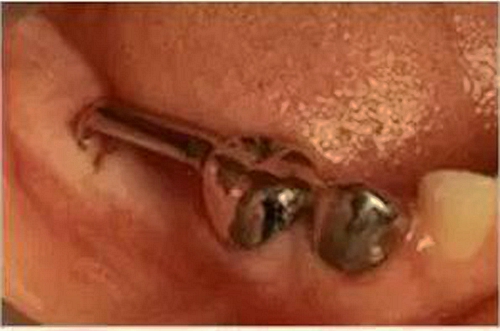

①(全冠)帶環(huán)絲圈式保持器

5.jpg

這種間隙保持器由不銹鋼絲制成,戴在缺席牙位旁邊的牙齒冠上來(lái)固定,或是使用帶環(huán)絲的固定方式。

鋼絲與帶環(huán)或全冠連接,沿著空隙的兩側(cè)延伸到另一顆牙齒上,這樣就能起到保持間隙的作用,讓恒牙有足夠的間隙長(zhǎng)出而不發(fā)生擁擠。